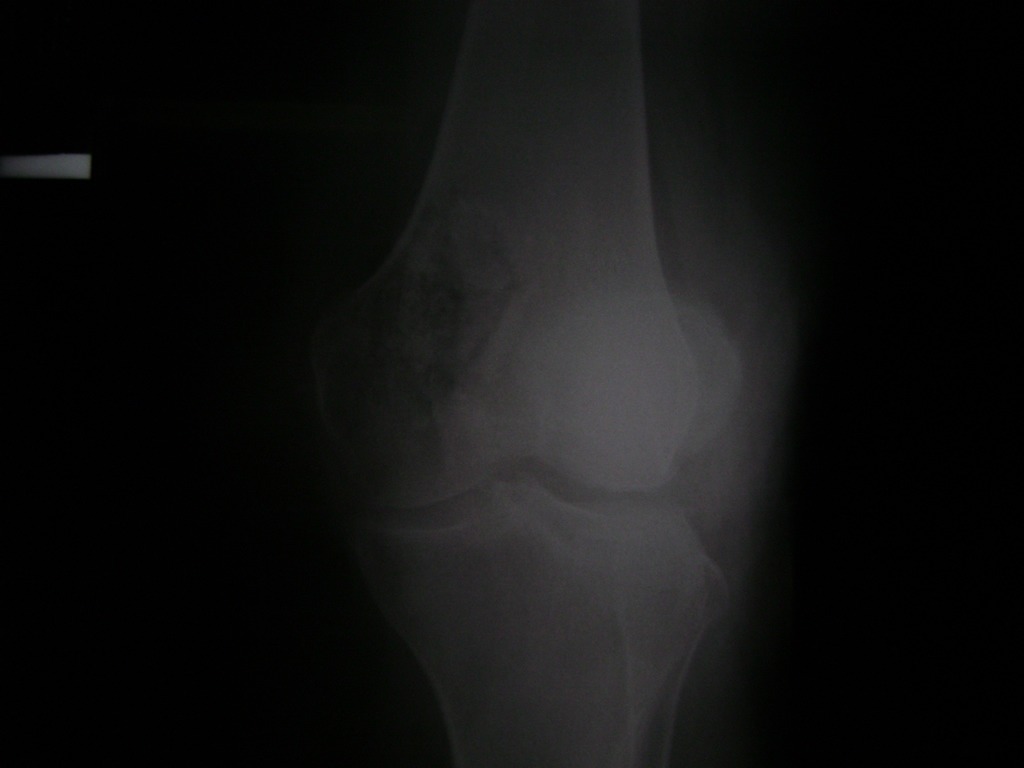

Cirugías de Calcaneo - Rodilla

La artroscopia de rodilla es un cirugía en el cual la estructura interna de la articulación es examinada ya sea para realizar un diagnostico o para realizar un tratamiento, este procedimiento se realiza utilizando un instrumento parecido a un pequeño tubo llamado artroscopio.